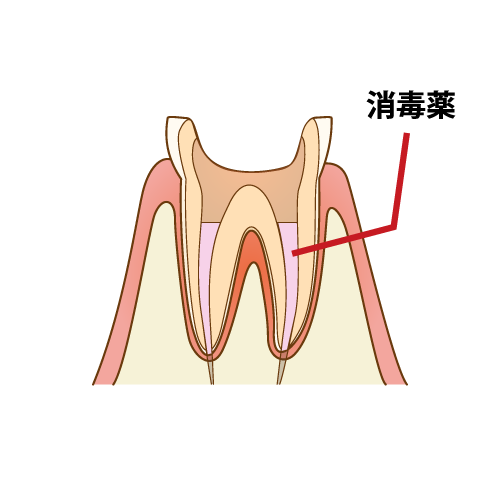

根管洗浄

神経を取り終わった後は、根管の内部が菌に侵されているので細い器具でお掃除をします。その時に根管の幅も広げていきます。

根管は元々細く洗浄がしにくい状態であり、薬を入れるスペースもありません。洗浄しつつ広げていくことで、細菌を除去しながら消毒液が先端まで行き渡り、薬が緊密に詰められるようにスペースを確保していきます。

根管充填